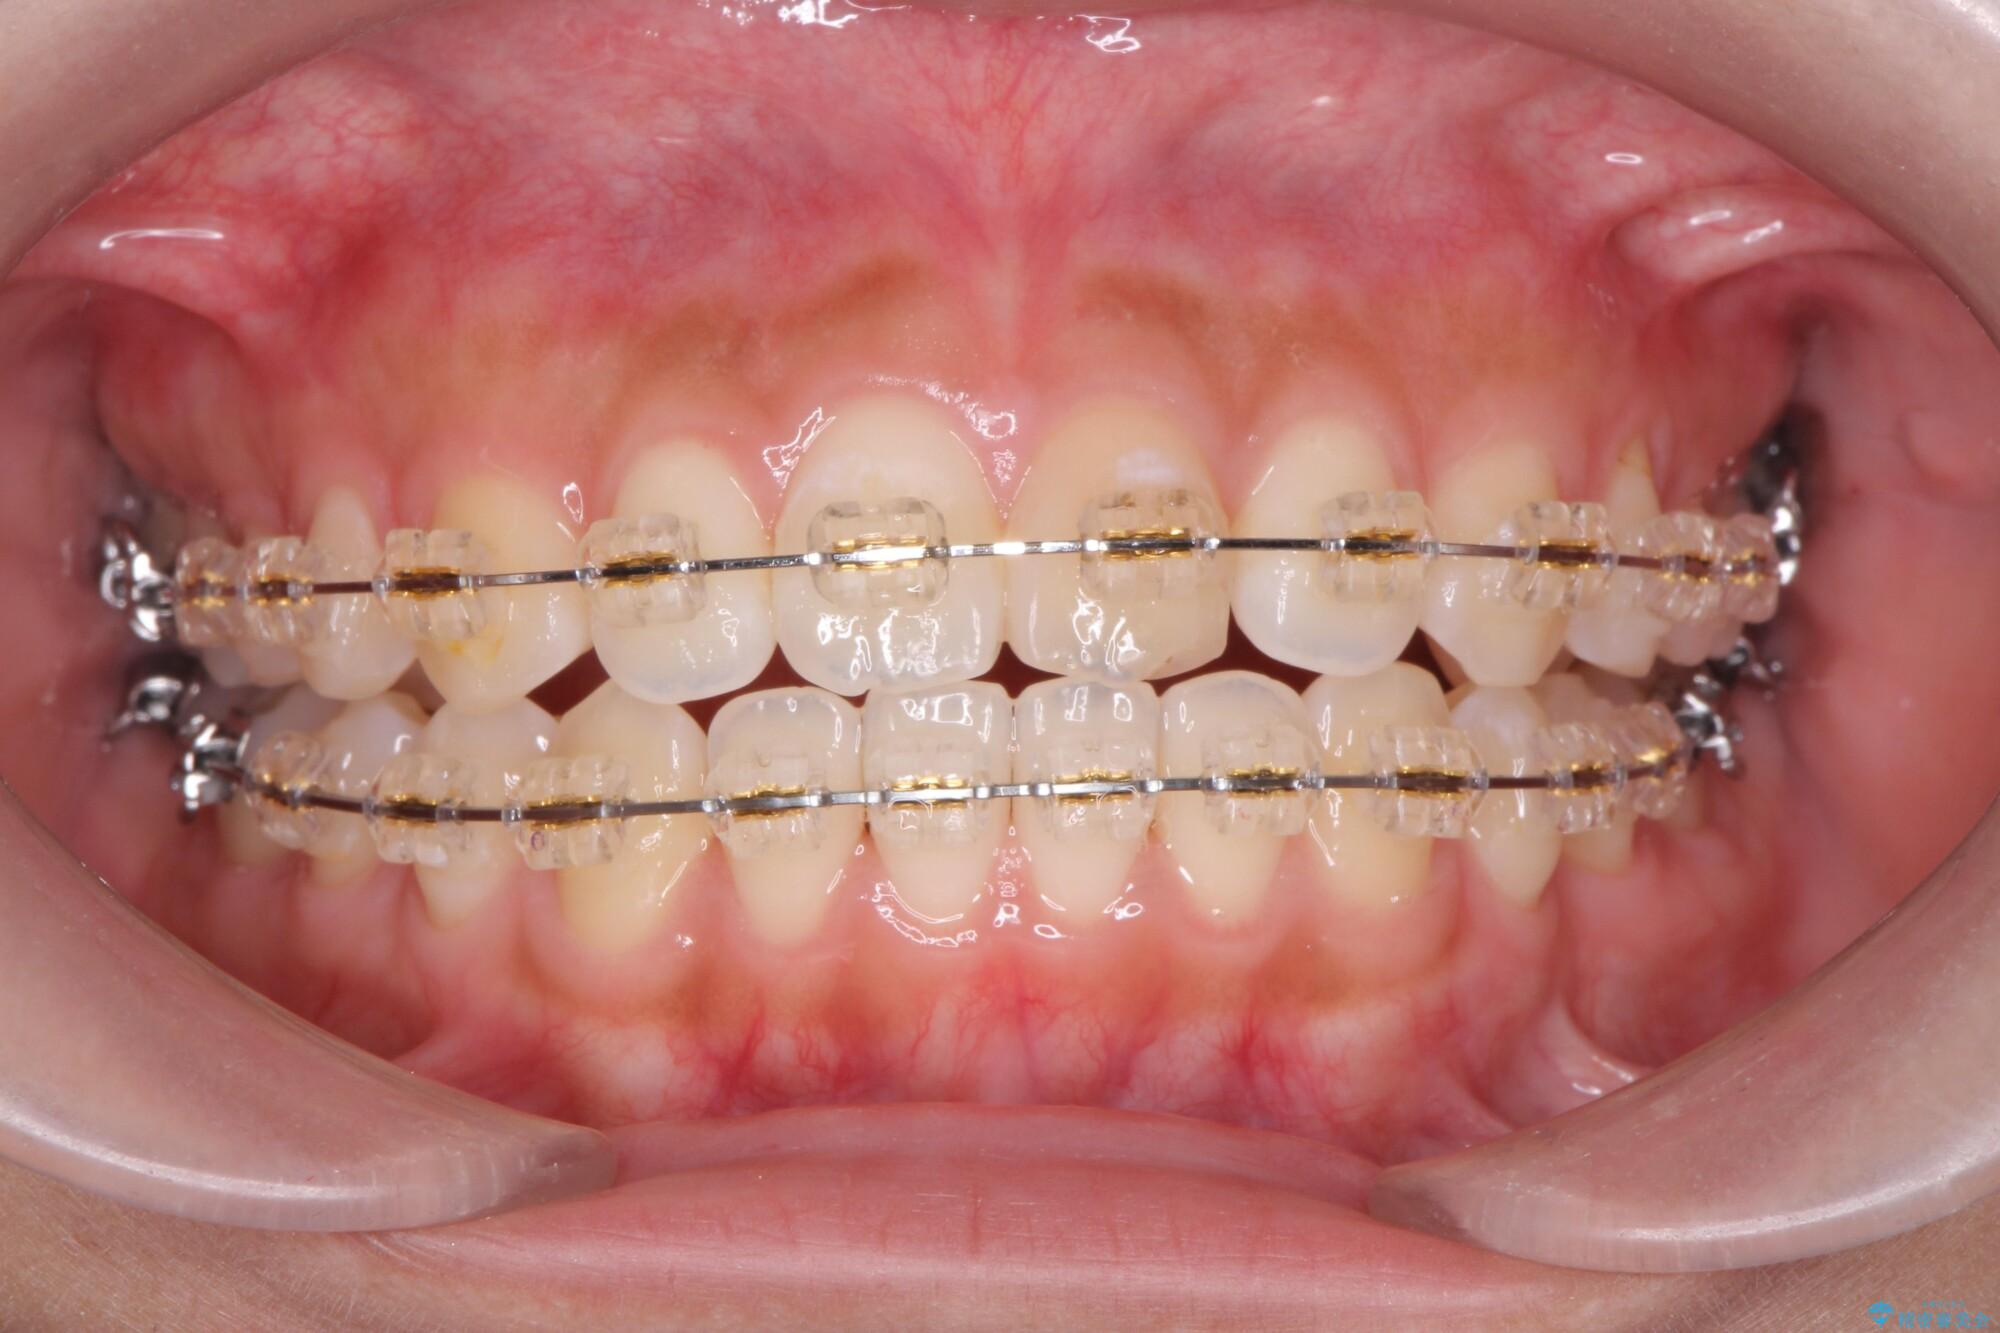

マルチブラケットを用いた非抜歯のワイヤー矯正で噛み合わせと歯並びを改善していきます。

1年で歯並び、嚙み合わせともにしっかりと改善されました。

患者様にも、非常に噛みやすくなったと喜んでいただくことができました。